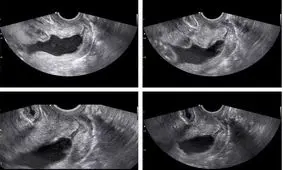

سونوگرافی آنومالی یک نوع اسکن برای تشخیص ناهنجاری های احتمالی جنین است که در سه ماهه دوم بارداری انجام می شود و معمولاً اسکنی دقیق است.

سونوگرافی آنومالی اسکن ۲ بعدی برای مادران بارداری است که بایستی رشد طبیعی کودک را بر اساس تجویز پزشک متخصص زنان و زایمان، بررسی کنند